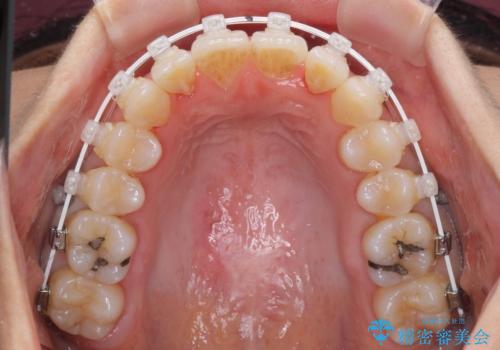

- 矯正装置

- 審美装置

上顎前歯の叢生が解消されると出っ歯になることが分かっていたので、両側奥歯付近にアンカースクリューを入れ、出っ歯を改善するためのゴムかけを行いました。

ゴムかけを頑張っていただいたので、当初の予定通り、1年強で治療を終えることができました。